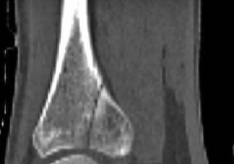

The distal tibia is characterized by a transition from the dense, triangular diaphyseal cortical bone to the thin, cancellous metaphyseal flare. This anatomical transition creates a significant mismatch between the relatively narrow intramedullary nail and the wide distal metaphysis. This discrepancy is the primary driver of malalignment during nailing, commonly leading to valgus and procurvatum deformities if not actively managed.

Image

The tibial plafond itself is concave in the sagittal plane and convex in the coronal plane, articulating with the talar dome. The lack of muscular coverage over the anteromedial aspect of the distal tibia renders the soft tissue envelope exceptionally vulnerable to trauma and surgical insult. The vascular supply to the distal tibia is heavily reliant on the periosteal network, derived from branches of the anterior and posterior tibial arteries. Intramedullary nailing, by avoiding extensive periosteal stripping, respects this critical vascular anatomy.